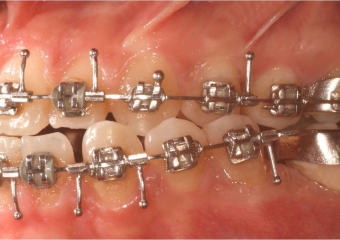

Mordida perfil inicial

Mordida perfil final